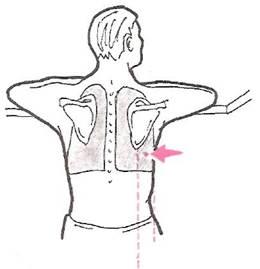

Техника плевральной пункции (торакоцентеза)

Торакоцентез проводится под местной анестезией, обычно в VII межреберье (но не ниже VIII ребра) между задней подмышечной и лопаточной линиям (рис. 30). Пункцию проводят по верхнему краю нижележащего ребра, так как по нижнему краю проходят межреберные сосуды и нервы (рис. 31). Срез иглы должен быть направлен вниз (к ребру). Предварительно тщательно исследуют больного, в том числе используя рентгенологический или ультразвуковой метод, для того чтобы получить информацию о местоположении верхнего уровня жидкости. Во время процедуры торакоцентеза больной сидит на стуле, лицом к спинке, свободно положив на нее руки и расслабив мышцы шеи.

Рис. 30.

Положение пациента и место прокола грудной стенки при проведении торакоцентеза.

Рис. 31.

Схема плевральной пункции.

Возможно также положение больного на краю кровати; тогда руки укладывают на прикроватный столик.

Непосредственно перед проведением торакоцентеза врач перкутирует грудную клетку и еще раз определяет уровень жидкости, делая отметку на коже. Кожу спины обрабатывают антисептическим раствором (обычно спиртовым раствором йода), после чего место пункции обкладывают стерильным материалом.

Кожу в месте прокола инфильтрируют раствором анестетика (новокаин, лидокаин), создавая «лимонную корочку». Затем анестезируют более глубоко расположенные ткани (подкожную клетчатку, надкостницу, плевру), медленно продвигая иглу, надетую па шприц, по верхнему краю ребра и постоянно инфильтрируя ткани анестетиком. По мере приближения к плевре введение каждой порции анестетиком чередуют с подтягиванием поршня шприца на себя. Когда в шприце появляется содержимое плевральной полости, иглу извлекают, надевают на шприц толстую и длинную пункционную иглу и медленно и осторожно проводят ее тем же путем в плевральную полость, поддерживая разряжение в шприце.